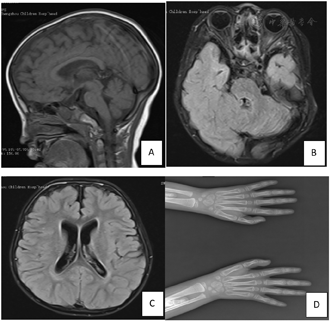

血常规、肝肾心功、丙酮酸、乳酸、同型半胱氨酸、甲状腺功能、血、尿代谢筛查均未见异常。头颅磁共振成像(magnetic resonancei maging,MRI)平扫示双侧额颞部蛛网膜下腔略宽,内部血管流空信号稍多,双侧眼眶外侧壁及周围软组织内见多发迂曲线状异常信号。右额叶点状FLAIR稍高信号--髓鞘发育不良;左顶叶片状FLAIR高信号,考虑脱髓鞘改变(图1A~C)。脑干诱发电位示ABR:左侧70dB Ⅲ-V峰间期>I-Ⅲ峰间期,V波波幅<I波波幅1/2波形差,Ⅲ波波幅明显低,波形较差,右侧70dB各波潜伏期及峰间期均正常,V波波幅<I波波幅1/2波形差,Ⅲ波波幅明显低,波形较差,双侧阈值20dB;ASSR:双侧阈值20dB;FVEP:双侧未见明显异常。心脏彩超:房间隔缺损Ⅱ型,二尖瓣少量返流。双手正位片:双侧拇指远节指骨骨骺形态欠佳(图1D)。双髋关节正位片:未见明显异常。24小时视频脑电图:正常。精神科B类量表评定:运动相当于18个月龄,社会适应相当于18月,智力相当于11月,原始总分47分,DQ<47分,MI<44。